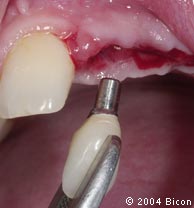

59. | 作减张切口,以便于一体化基台冠的就位。 |

60. | 试戴一体化基台冠,确定其是否合适。 |